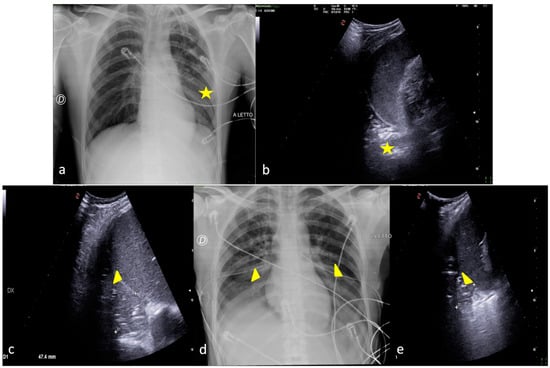

2.1. Atelectasis

2.2. Pneumonia

2.3. Pleural Effusion